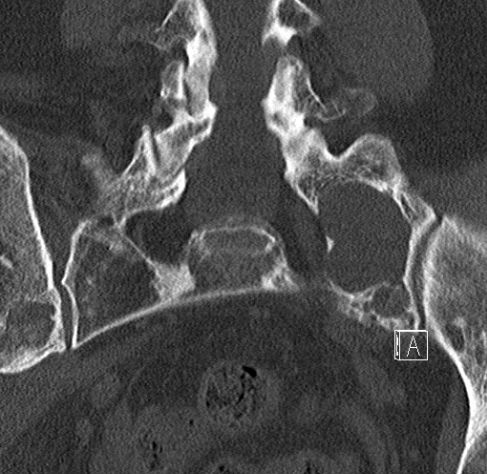

60-jährige Frau mit metastasierten Mammakarzinom. Jetzt

segmentförmige Schmerzen der linken Thoraxwand. das CT zeigt einen diskreten

Weichteiltumor mit Infiltration des Neuroforamens.![]() | |||||||||